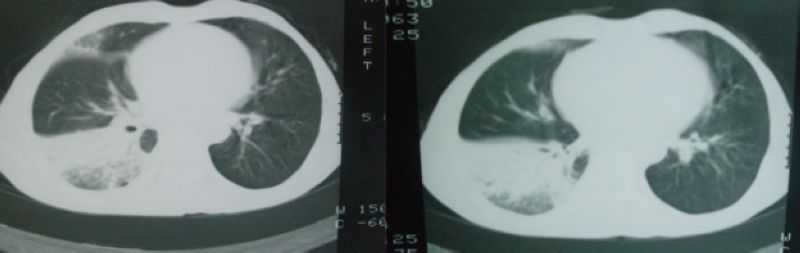

以下是引用随光逐影在2008-4-16 18:45:00的发言:[br]考虑为:肺部感染性病变;建议:抗炎治疗一周后复查。